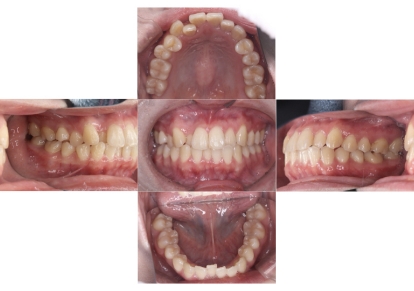

症例1

上顎前突、叢生

抜歯

ブラケット矯正

上下顎叢生、上顎前突(出っ歯、上下の前歯のガタガタ)のケースです。

装置はラビアル(上下表側)で、上顎の小臼歯を2本抜歯を行っています。抜歯したスペースを使って、上の前歯の後方移動と叢生(ガタガタ)と出っ歯の改善を行っています。下は歯と歯の間にIPR(隣接面削合)を行い、スペースを確保し、叢生の改善を行っています。

主訴 前歯のガタガタと出っ歯が気になる。

年齢・性別 47歳 女性

お住まいの地域 神奈川県川崎市

治療方針 抜歯スペースおよびIPRを利用して上前歯の叢生(ガタガタ)の改善

抜歯部位 上顎左右第一小臼歯

使用装置 ラビアル(上下表側)、顎間ゴム

治療期間 2年0か月

治療回数 15回

リテーナー クリアリテーナー

BEFORE

AFTER